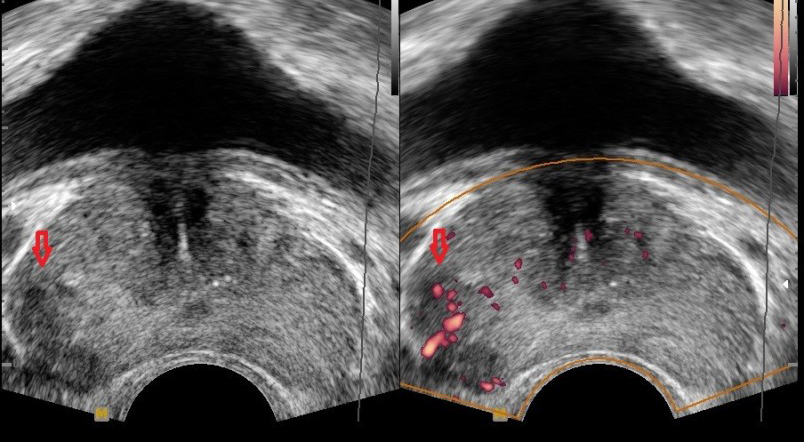

전립선암은 주로 전립선의 바깥쪽 부분인 말초대(Peripheral Zone)에서 발생합니다. 이 때문에 종양이 요도를 압박할 정도로 커지기 전까지는 증상이 나타나지 않는 경우가 많지만, 아래와 같은 비뇨기계 증상 및 전신 증상이 나타나기 시작하면 반드시 정밀 검사가 필요합니다.

- 전립선암 선별검사(PSA 검사) 필수

- 대상: 특별한 증상이 없더라도 50세 이상 남성은 매년 1회 혈액 PSA(전립선 특이항원) 검사와 직장 수지 검사를 받는 것이 권장됩니다.

- 전립선암의 초기 증상이 전립선 비대증과 매우 유사하더라도, **배뇨 증상(빈뇨, 잔뇨감, 세뇨 등)**이 장기간 지속되고 점점 악화된다면 단순히 나이 탓으로 여기지 말고 비뇨의학과 전문의를 찾아 정확한 원인을 진단받아야 합니다.